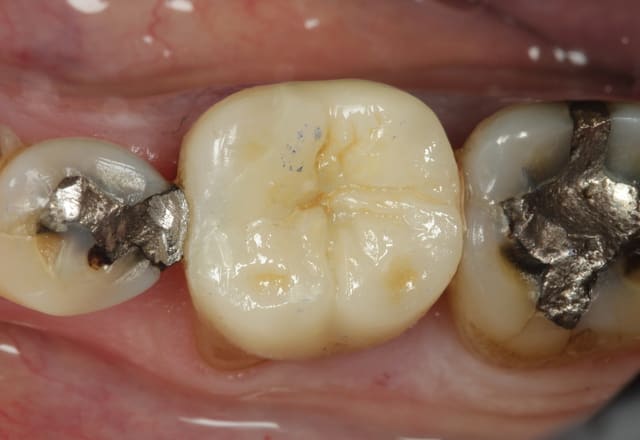

Si le prothésiste avait pu simuler au milieu de cet onlay un petit amalgame avec des bords vieillissant, le mimétisme aurait été parfait...

Toute blague mise à part, très joli onlay, aussi bien la morphologie que les joints quasi invisibles... Je vais faire quelques prières pour que la dent ne se nécrose pas rapidement!

En gros c'est une couronne 9/10ème !

C'est un cas limite.

Mais le risque c'est de se retrouver a devoir dépulper et faire une couronne, alors pourquoi le faire tout de suite.